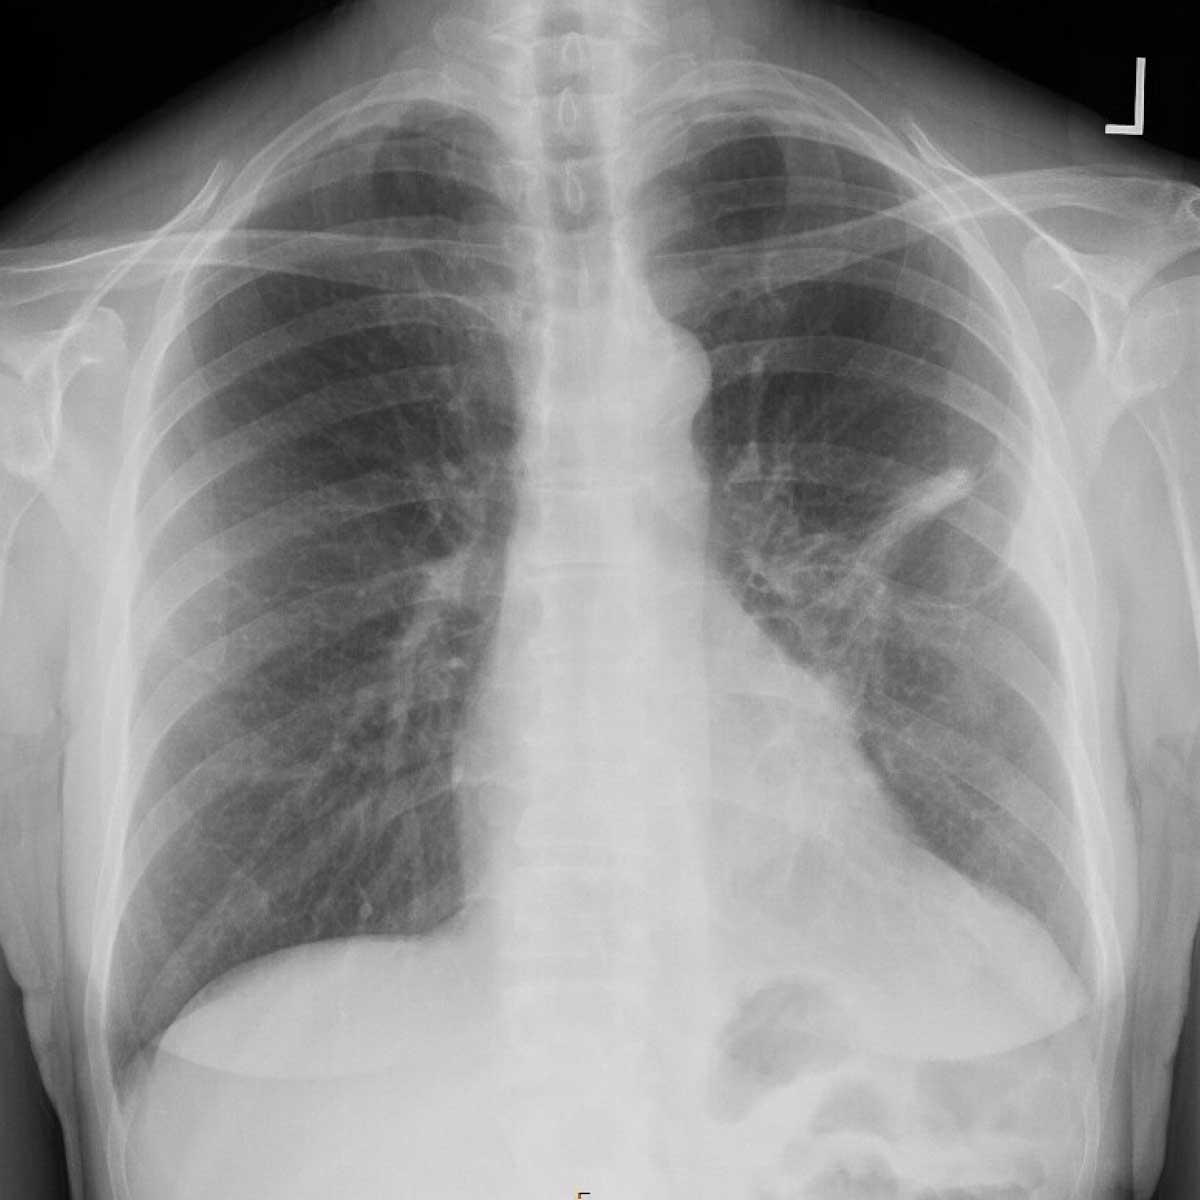

A scan image of Laura Dehlendorf’s lungs before her procedure

The lung scan, taken before surgery, showing a nodule on Dehlendorf’s left lung.